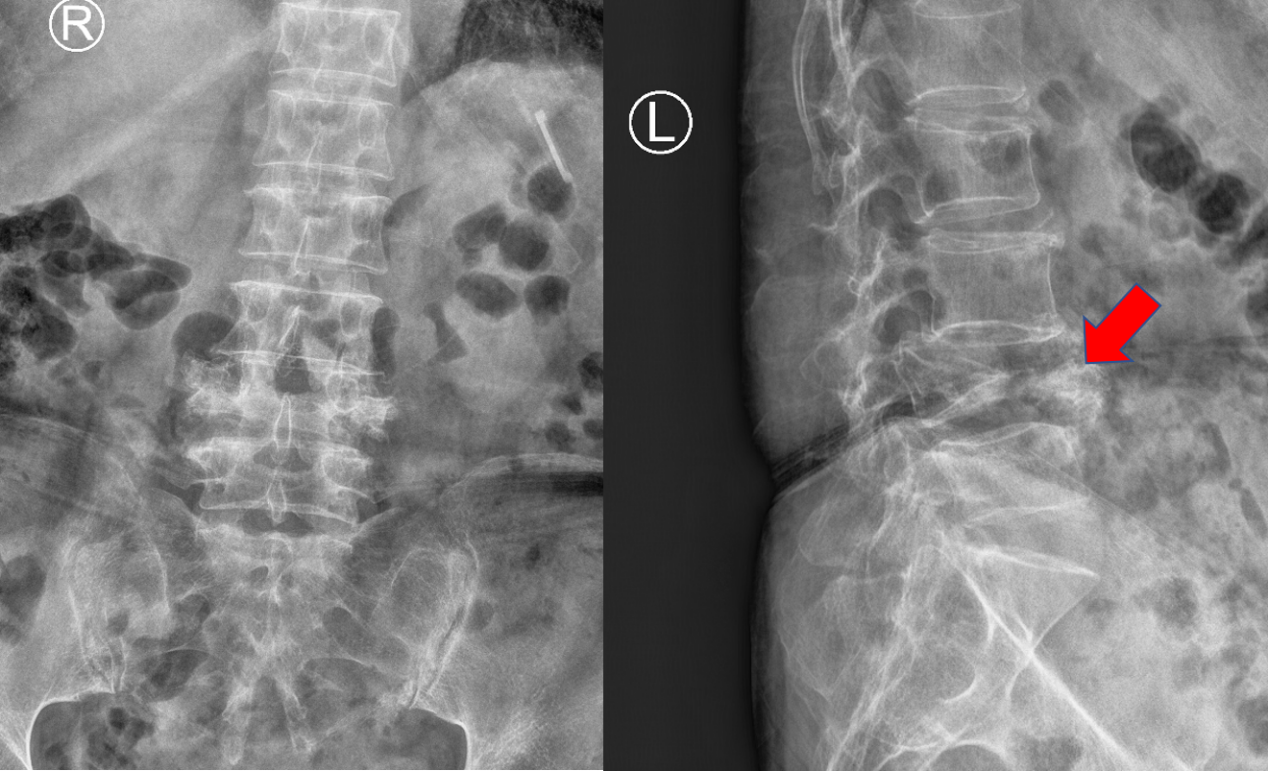

L4椎体陈旧性骨折,椎体高度塌陷严重

患者L4椎体几乎完全压缩,骨块已突入椎管,椎管严重狭窄

L4水平椎管狭窄明显,造成患者双下肢乏力、麻木